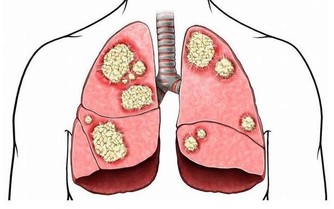

【1】尿路感染

相信大家在生活當中也都聽說過尿路感染的問題,尤其是在晚上睡覺過程當中,夜尿增多,就可能是尿路感染引起的,如果局部炎症感染沒有得到治療,炎症不斷的刺激,就會導致患者出現尿頻尿急夜尿增多的表現。

而且患者在排尿的過程當中,也會出現排尿疼痛,藥後滴瀝、尿道口還有白色的分泌物,嚴重的時候身體也會出現發熱,這個時候也希望大家一起重視進行合理的治療。